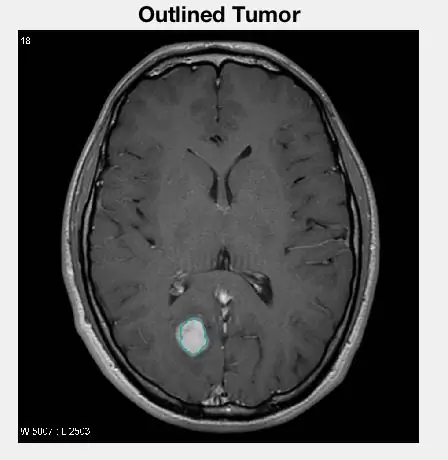

Шаг 5: выделение опухоли

Выделение опухоли

Наши последние операции, выполненные с изображением, позволили нам наложить цветную форму вокруг опухоли на исходном изображении, чтобы выделить ее для зрителя. Для выполнения этого шага мы использовали код:

BWoutline = bwperim (BW); % найти периметр опухоли на двоичном изображении SE3 = strel ('квадрат', 3); % использовать элемент структурирования для увеличения толщины контура на 3 пикселя в ширину

outlineImg = II;

ThickOutlines = imdilate (BWoutline, SE3); % увеличить толщину контура

OutlineImg (ThickOutlines) = 50; % установить цвет контура

подзаговор (1, 4, 4);

imshow (outlineImg); % отобразить очерченную опухоль на исходной МРТ

title («Обрисованная опухоль»);

Для этого мы сначала использовали другую морфологическую функцию, чтобы найти внешний периметр изолированной опухоли. Когда мы достигли периметра, мы установили для соответствующих пикселей исходного изображения значение 50, чтобы изменить их цвет и сделать их ярче. Наконец, после этого мы отобразили изображение на подзаголовке с другими желаемыми изображениями, полученными ранее.